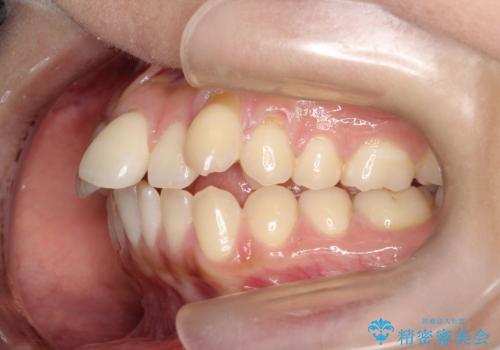

- 矯正装置

- 審美装置

- 前歯の凸凹を主訴に来院されました。

予想治療期間2年でしたが、実際は1年半ほどで終了し満足していただきました。

小臼歯抜歯(上顎4番)して矯正治療を行なったことで、口元もスッキリしました。